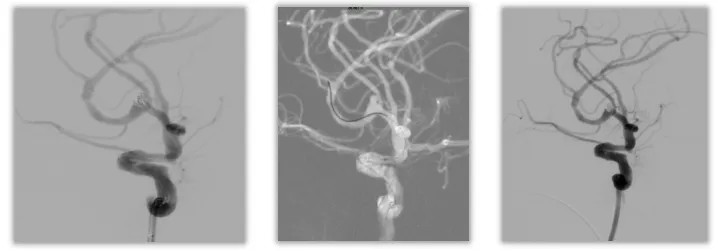

DSA:右侧大脑中分叉部动脉瘤,瘤体:3.1mm×3.2mm×2.9mm,瘤颈3.0mm,相对宽颈。

结合最新文献报道,破裂动脉瘤应在出血后尽早进行手术或血管内治疗,最好在发病后 24 小时内进行。考虑该患者长期服用阿司匹林,开颅手术创伤大、造成围手术期大出血的风险高,综合考虑,建议急诊行动脉瘤栓塞联合钻孔引流手术。

1、破裂动脉瘤瘤壁菲薄,在微导管到位及填塞弹簧圈的过程中,再次破裂出血的风险高。

2、动脉瘤相对宽颈,需支架辅助栓塞,服用双联抗血小板药物,增加围手术期出血和缺血事件发生的概率。

3、动脉瘤体积较小,瘤内操作空间狭小,增加栓塞过程中破裂出血的概率。

对此,我们采用Atlas支架辅助栓塞,填塞4枚弹簧圈,成功栓塞动脉瘤。